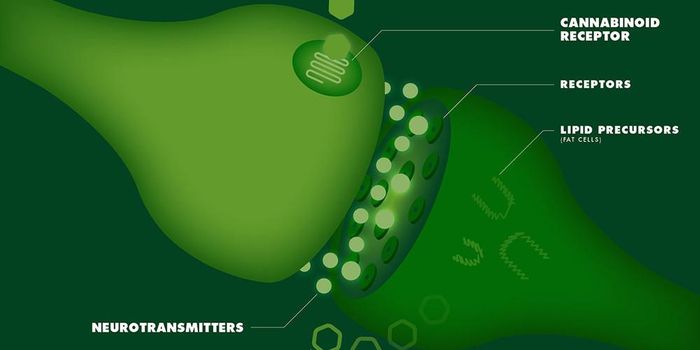

APR 12, 2018Cannabis SciencesEndocannabinoids are lipophilic ligands that act as signaling molecules which are synthesized from glycerophospho ...

APR 26, 2018Cannabis SciencesThe endocannabinoid system is the body’s system that regulates an array of other systems in the body. It wor ...

NOV 01, 2018Cannabis SciencesMany of us are aware of the relatively new discovery of the endocannabinoid system (ECS). This is the system which is hi ...

NOV 23, 2018Cannabis SciencesThe evidence that the endocannabinoid system (ECS) is intimately involved in food intake has been steadily increasing. T ...

FEB 08, 2018Cannabis SciencesThe endocannabinoid system is a unique regulatory neurotransmitter system in the body.